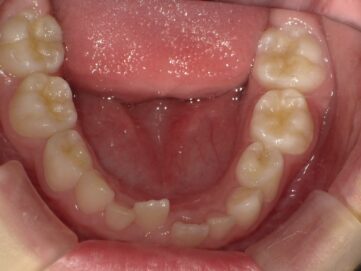

歯並びの悪い原因としては顎の急な成長によるものが多く、装置で顎を広げる事で歯が綺麗に並ぶスペースを確保します。

急速拡大装置で上顎の拡大が進むと、下顎の骨も調整する必要が出てきます。その際に使う装置がリンガルアーチです。下顎の骨は上顎の骨と作りが違います。下顎はひとつの骨で構成されているので、上顎と同じように拡大させることができません。内側に傾いている歯を起こすようにして歯列部分だけを拡げていきます。この装置も固定式の装置となっており、歯の裏側に装着しますので目立たない見た目となっています。